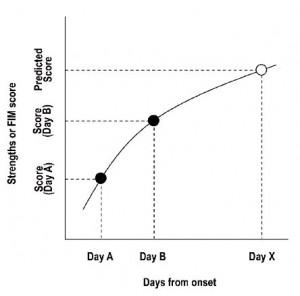

Suzuki M, Sugimura Y, Yamada S, Omori Y, Miyamoto M, Yamamoto J. (2012) Predicting recovery of cognitive function soon after stroke: differential modeling of logarithmic and linear regression.PLoS One. 2013;8(1):e53488. doi: 10.1371/journal.pone.0053488. Epub 2013 Jan 11.

Suzuki M, Omori Y, Kirimoto H, Sugimura S, Miyamoto M, Sugimura Y, Yamada S. (2011) Predicting Recovery of Bilateral Upper Extremity Muscle Strength after Stroke. Journal of Rehabilitation Medicine. 43:935-943.